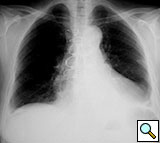

Figure 11. Fourteenth postoperative day image showing sternal wire migration in the caudal sternum segment (*).

Figure 12. Postoperative sternal reconstruction showing sternal fixation with DSS (2 and 3 units in the right and left hemisternum, respectively